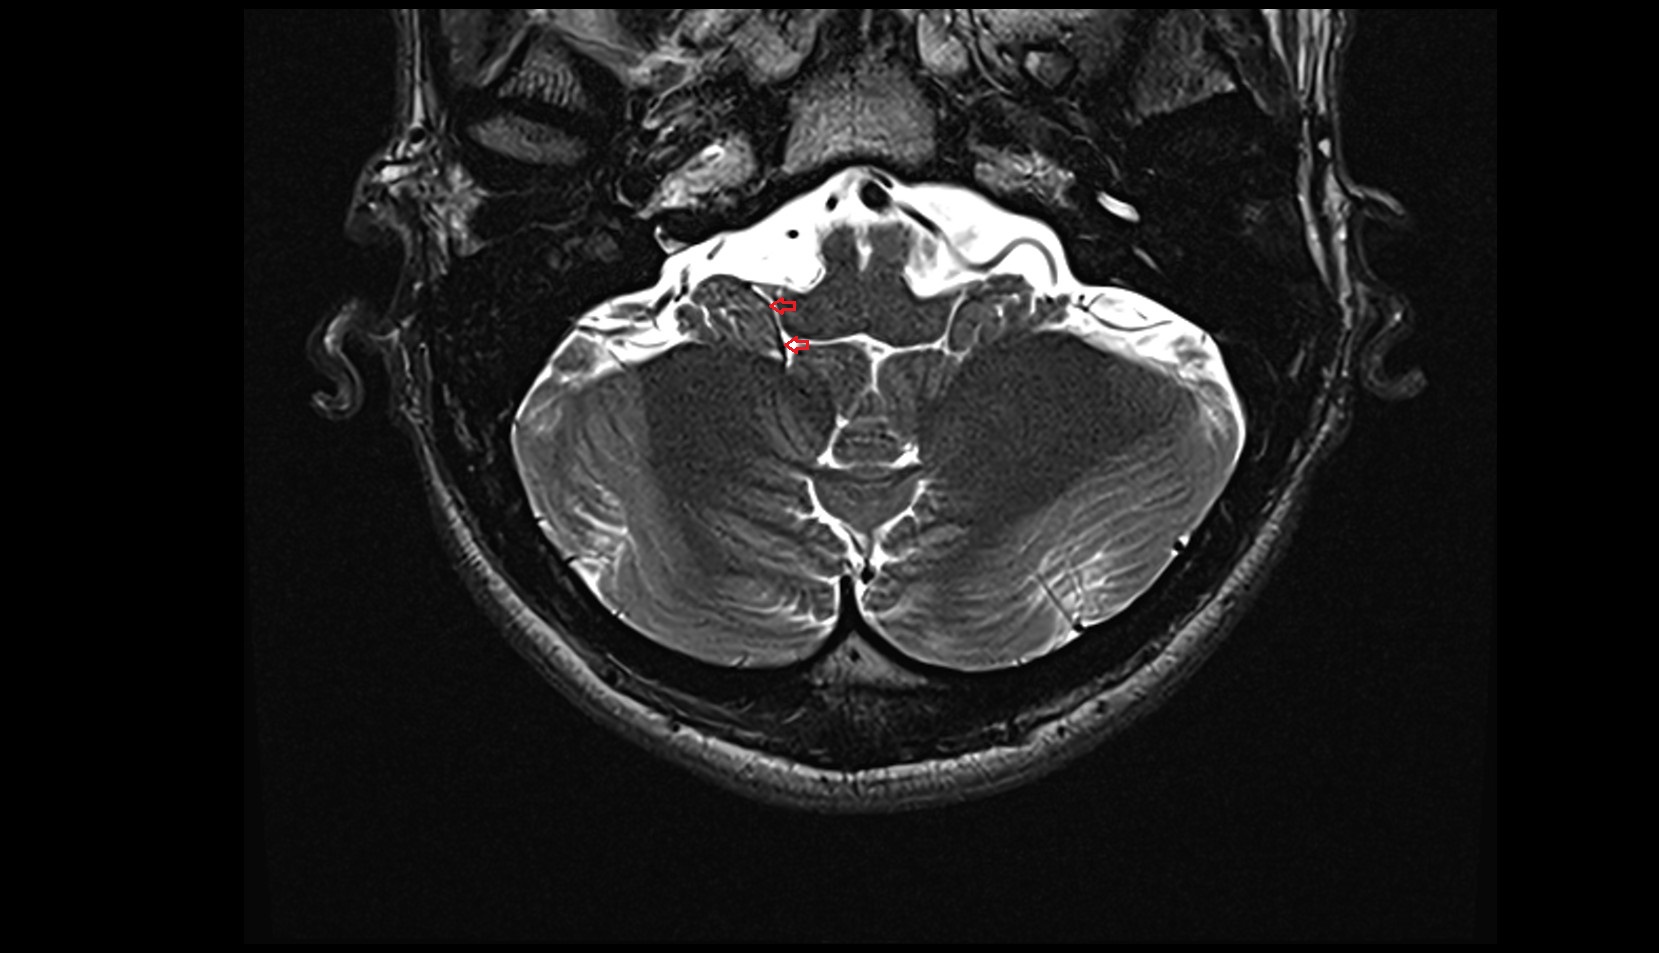

- Flocculus

- Cerebellar tonsil (H IX)